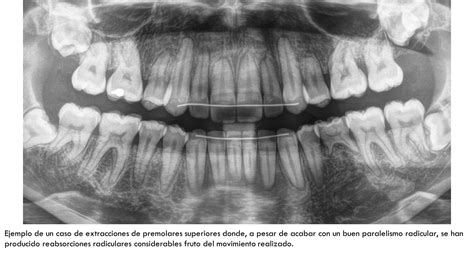

- Tecnología utilizada: Una clínica equipada con tecnología de vanguardia -como escáneres intraorales, radiología 3D o cirugía guiada por ordenador- puede ofrecer diagnósticos más precisos y tratamientos menos invasivos, con mejores resultados a largo plazo.

Forma y espiras del Implante: cada modelo de implante y dependiendo sobre todo del desarrollo en I+D que haya conllevado su desarrollo presenta una morfología y disposición de las espiras distintas. Ambos conceptos suponen la primera base del éxito de la osteointegración y la perdurabilidad del implante en boca.

Fase protésica: además del propio implante, una parte importantísima es la forma de unir dicho implante a la corona ó a la prótesis correspondiente, ya que ésta unión es la que va a distribuir todas las fuerzas bucales. Por estos motivos en SALUD DENTAL BLANCO sólo trabajamos con implantes con todas las certificaciones a nivel Europeo y Español, ofreciendo a nuestros pacientes el tipo de implante que mejor se adapte a su caso y a su situación.